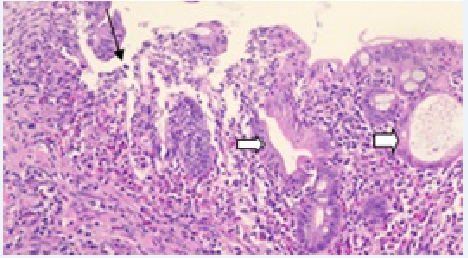

Histopathology revealed chronic duodenitis, eggs and adult forms of Strongyloides stercoralis, ulcerated chronic colitis in mild activity, with microabscesses of crypts and architectural glandular alterations. No signs of malignancy (Figures 3 & 4).

Figure 3 Histopathological examination of duodenal ulcers with chronic duodenitis, eggs end some adult forms of Strongyloides stercoralis, focis of ulceration and fibrino-leukocyte crust, without signs of malignancy - HE-200x.

Figure 4 Colonic mucosa with microabscesses of crypts (black arrow) and architectural glandular distortion (white arrow) - HE-200x.